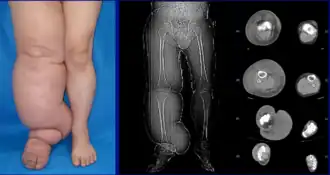

Lower extremity lymphedema | |

Lymphedema can occur in both the upper and lower extremities, and in some cases, the head and neck. Assessment of the extremities first begins with a visual inspection; color, presence of hair, visible veins, size and any sores or ulcerations are noted. Lack of hair may indicate an arterial circulation problem.[34] In cases of swelling, the extremities' circumference is measured over time for reference. In early stages of lymphedema, elevating the limb may reduce or eliminate the swelling. Palpation of the wrist or ankle can determine the degree of swelling; assessment includes a check of the pulses. The axillary or inguinal lymph nodes may be enlarged due to the swelling. Enlargement of the nodes lasting more than three weeks may indicate infection or other illnesses (such as sequela from breast cancer surgery) requiring further medical attention.[34]